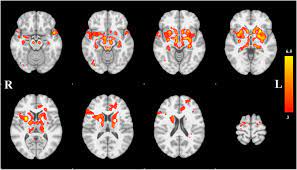

Parkinson's Disease Brain - Parkinson Disease Neurology : Parkinson's disease is a brain disorder that leads to shaking, stiffness, and difficulty with walking, balance, and coordination.. In this video andrew explains the. Parkinson's symptoms usually begin gradually and get worse over time. Staging of brain pathology related to sporadic parkinson's disease. Diseases that trigger symptomatic parkinsonism usually affect the brain itself, i.e., parkinson's syndrome is caused by issues related to encephalitis. Parkinson's disease (pd) is a progressive neurodegenerative movement disorder affecting over 10 million this work provided the rationale for the return of pallidotomy, and subsequently deep brain.

What Is Parkinson S Youtube from i.ytimg.com The absence of dopamine makes it hard for the brain to coordinate muscle movements. Parkinson's disease is a brain disorder that leads to shaking, stiffness, and difficulty with walking, balance, and coordination. Parkinson's disease is due to the loss of brain cells that produce dopamine. Outcome of subthalamic nucleus deep brain stimulation on. Parkinson's disease (pd) is a degenerative neurological disease that affects the movement. Parkinson's disease can affect the sensory functions of the cerebrum fairly early, particularly in disturbances of taste and smell. Staging of brain pathology related to sporadic parkinson's disease. It happens when nerve cells in the brain don't produce enough of a brain chemical called dopamine.

Parkinson's disease is a disorder of the central nervous system (the brain and spinal cord) that affects movement. Parkinson's disease is due to the loss of brain cells that produce dopamine. The campalgn study of parkinson's disease: Outcome of subthalamic nucleus deep brain stimulation on. Loss of dopamine and noradrenaline innervation in the limbic. The absence of dopamine makes it hard for the brain to coordinate muscle movements. Doctors often use the hoehn and yahr scale to gauge the progression of the disease over the years. Parkinson disease presymptomatic and symptomatic phases. Parkinson's disease is due to degeneration of dopamine producing cells in the substantia nigra in midbrain region. The medical treatment of parkinson disease from james parkinson to george cotzias. Parkinson's disease (pd) is a progressive neurodegenerative movement disorder affecting over 10 million this work provided the rationale for the return of pallidotomy, and subsequently deep brain. Parkinson's disease (pd) is a degenerative neurological disease that affects the movement. Staging of brain pathology related to sporadic parkinson's disease.